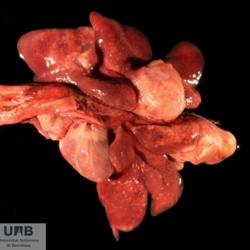

Pàgina anterior de 637 Pàgina següent 3181 total Porcine Specie: Porcine Organ: Heart Lesion: Endocarditis Lesion modifier: Endocarditis - Valvular Disease: - Position: 33 (7 views) Porcine Specie: Porcine Organ: Heart Lesion: Endocarditis Lesion modifier: Endocarditis - Valvular Disease: - Not viewed Canine Specie: Canine Organ: Intestine Lesion: Obstruction Lesion modifier: - Disease: - Files/Expedient: N-165/15 Position: 252 (1 views) Feline Specie: Feline Organ: Lung Lesion: Carcinoma Lesion modifier: Carcinoma - Adenocarcinoma Disease: - Files/Expedient: N-161/15 Position: 136 (2 views) Canine Specie: Canine Organ: Thoracic cavity Lesion: Atelectasis Lesion modifier: - Disease: - Files/Expedient: N-160/15 Not viewed Pàgina anterior de 637 Pàgina següent Títol Select...Avian (Exotic) (110)Avian (Poultry) (76)Bovine (317)Canine (935)Caprine (47)Equine (257)Feline (326)Ferret (19)General (127)Marine mammal (22)Non-human primate (20)Ovine (328)Porcine (379)Rabbit (61)Reptile (38)Rodent (28)Wildlife (91) Format Select...- (60)Abomasum (37)Adrenal gland (10)Blood (7)Blood vessel (50)Body as a whole (19)Bone (57)Bone marrow (21)Brain (93)Cloaca (1)Diaphragm (2)Ear (5)Esophagus (39)Eye (16)Fetus (12)Gallbladder (23)Gizzard (2)Heart (265)Intestine (356)Joint (32)Kidney (443)Larynx (5)Liver (326)Lung (264)Lymph node (91)Mammary gland (10)Mediastinum (1)Muscle (22)Nasal cavity (22)Nerve (7)Omasum (5)Oral cavity (63)Ovary (14)Oviduct (8)Pancreas (7)Parathyroid (5)Penis (10)Peritoneum (65)Pharynx (9)Pituitary gland (6)Placenta (7)Prostate (8)Proventriculus (3)Reticulum (1)Rumen (28)Sinus (7)Skin (181)Spinal cord (15)Spleen (105)Stomach (125)Teeth (1)Testicle (11)Thoracic cavity (31)Thymus (13)Thyroid gland (5)Tongue (32)Tonsils (11)Trachea (11)Urethra (5)Urinay bladder (61)Uterus (27)Vagina (1)Vulva (1)Yolk sac (1) Cobertura Select...- (152)Abomasitis (26)Abscess (27)Acidosis (1)Adenocarcinoma (20)Adenoma (9)Aerosacculitis (6)Agenesis (1)Agnathia (1)Alopecia (7)Amyloidosis (12)Aneurysm (6)Angiectasis (1)Anthracosis (1)Arteritis (11)Arthritis (15)Arthrogryposis (6)Artifact (4)Ascites (13)Atelectasis (8)Atherosclerosis (5)Atresia (1)Atrial septal defect (2)Atrophy (10)Autolysis (7)Bronchitis (6)Bronchopneumonia (26)Cachexia (2)Carcinoma (103)Cardiomyopathy (19)Cellulitis (2)Chemodectoma (4)Cholangiohepatitis (4)Cholangitis (19)Cholecystitis (4)Cholestasis (5)Chondrodysplasia (2)Chondrosarcoma (2)Chronic passive congestion (13)Chylothorax (2)Cirrhosis (6)Coelomitis (3)Coenurus cerebralis (4)Colitis (40)Congestion (17)Conjunctivitis (5)Coronitis (3)Cryptorchidism (3)Cyst (25)Cystitis (24)Dermatitis (69)Diaphragmatic hernia (4)Dilation (28)Discospondylitis (1)Disseminated intravascular coagulation (7)Dyschondroplasia (1)Dysplasia (29)Ectopia cordis (1)Ectopic ureter (1)Edema (55)Emphysema (5)Encephalitis (5)Endocardiosis (14)Endocarditis (26)Endometritis (5)Enteritis (118)Enterolith (6)Epulis (3)Esophagitis (14)Fasciitis (1)Fibrosis (7)Fibrous osteodystrophy (8)Fistula (1)Folliculitis (3)Fracture (2)Gastritis (34)Gingivitis (5)Glioma (8)Glomerulonephritis (21)Glossitis (25)Glycogenosis (1)Gout (8)Granuloma (2)Granulosa cell tumor (4)Hemangioma (9)Hemangiosarcoma (46)Hematoma (8)Hemoglobinuria (2)Hemopericardium (12)Hemoperitoneum (2)Hemorrhage (100)Hemosiderosis (7)Hemothorax (2)Hepatitis (78)Hernia (11)Histiocytosis (3)Hydatid cyst (11)Hydrocephalus (9)Hydrometra (1)Hydronephrosis (22)Hydropericardium (6)Hydrothorax (3)Hydroureter (5)Hyperkeratosis (8)Hyperostosis (4)Hyperplasia (37)Hypertrophy (9)Hypopigmentation (1)Hypoplasia (7)Hypopyon (1)Impaction (6)Infarction (63)Insulinoma (6)Intussusception (5)Jaundice (17)Laminitis (2)Laryngitis (2)Leiomyoma (5)Leukemia (13)Lipidosis (36)Lipoma (7)Lymphadenitis (45)Lymphadenopathy (7)Lymphangiectasia (6)Lymphangitis (5)Lymphoma (221)Malacia (11)Malignant melanoma (15)Mast cell tumor (11)Mastitis (8)Megaesophagus (2)Melanosis (3)Melena (4)Meningioma (6)Meningitis (6)Meningocele (2)Meningoencephalitis (5)Mesothelioma (5)Methemoglobinemia (2)Mineralization (10)Mucocele (5)Mucometra (1)Multilobular bone tumor (1)Mummification (3)Myelofibrosis (1)Myocarditis (4)Myositis (5)Necrosis (81)Nephritis (113)Nephroblastoma (6)Nephrosclerosis (1)Nephrosis (14)Neuritis (1)Obstruction (13)Omasitis (4)Omphalitis (1)Omphalophlebitis (7)Orchitis (4)Osteoarthrosis (5)Osteomyelitis (9)Otitis (2)Palatoschisis (3)Pancreatitis (3)Panniculitis (3)Papilloma (7)Parakeratosis (14)Patent ductus arteriosus (6)Peliosis hepatis (1)Perforation (17)Pericarditis (35)Peritonitis (39)Persistent right aortic arch (1)Pharyngitis (2)Pheochromocytoma (2)Phlebitis (2)Placentitis (6)Pleuritis (21)Pleuropneumonia (24)Pneumonia (109)Pneumothorax (3)Polycystosis (14)Polyp (5)Polyserositis (6)Posthitis (1)Proctitis (4)Prolapse (3)Prostatitis (3)Proventriculitis (1)Pyelonephritis (24)Pyometra (6)Pyothorax (4)Rhinitis (11)Rumenitis (6)Rupture (24)Salpingitis (3)Sarcoma (57)Sclerosis (1)Scoliosis (2)Seminoma (2)Sequestrum (2)Serous atrophy (14)Sinusitis (7)Splenitis (14)Splenomegaly (9)Spondylitis (6)Spondylosis (1)Stenosis (9)Stomatitis (32)Tenosynovitis (2)Teratoma (3)Thricobezoar (2)Thrombosis (16)Tonsilitis (4)Torsion (13)Tracheitis (4)Tympany (7)Typhlitis (8)Typhlocolitis (4)Ulcer (43)Urethritis (1)Urolithiasis (36)Uroperitoneum (1)Uveitis (1)Vasculitis (15)Ventricular septal defect (3)Volvulus (11) Matèria Select... - (14)- (1653)- (152)Abomasitis - Catarrhal (2)Abomasitis - Catarrhal-hemorrhagic (1)Abomasitis - Chronic (1)Abomasitis - Fibrinous-necrotizing (2)Abomasitis - Hyperplasic (5)Abomasitis - Hyperplasic - Chronic (1)Abomasitis - Necrotic (1)Abomasitis - Necrotizing (2)Abomasitis - Ulcerative (5)Adenocarcinoma (9)Aerosacculitis - Granulomatous (1)Amyloidosis - Chronic (1)Arteritis - Necrotic (2)Arteritis - Necrotizing (1)Arthritis - Chronic (4)Arthritis - Fibrinous-purulent (3)Arthritis - Serous (4)Arthritis - Subacute (1)Ascites - Serous (1)Atrophy - Serous (1)Bronchitis - Catarrhal (3)Bronchitis - Suppurative (1)Bronchopneumonia - Catarrhal-purulent (17)Bronchopneumonia - Fibrinous (1)Bronchopneumonia - Granulomatous (1)Bronchopneumonia - Purulent (1)Bronchopneumonia - Suppurative (5)Carcinoma - Adenocarcinoma (33)Carcinoma - Adenocarcinoma - Hepatocellular (2)Carcinoma - Adenocarcinoma - Mucinous (1)Carcinoma - Basosquamous (1)Carcinoma - Cholangiocellular (3)Carcinoma - Hepatocellular (4)Carcinoma - Metastatic (3)Carcinoma - Squamous cell carcinoma (13)Carcinoma - Transitional cell (2)Cardiomyopathy - Dilated (13)Cardiomyopathy - Hypertrophic (6)Cellulitis - Necrotizing (1)Cholangitis - Chronic (8)Cholangitis - Hyperplasic (3)Cholecystitis - Fibrinous-necrotizing (1)Coelomitis - Fibrinous (1)Coelomitis - Granulomatous (1)Colitis - Catarrhal (3)Colitis - Catarrhal-hemorrhagic (1)Colitis - Fibrinous (1)Colitis - Fibrinous-necrotizing (1)Colitis - Fibrinous-necrotizing (Diphtheritic) (6)Colitis - Granulomatous (2)Colitis - Hemorrhagic (4)Colitis - Hemorrhagic-necrotizing (3)Colitis - Necrotizing (2)Colitis - Ulcerative (6)Congestion - Chronic (2)Conjunctivitis - Hyperplasic (1)Conjunctivitis - Purulent (3)Coronitis - Ulcerative (1)Cystitis - Chronic (3)Cystitis - Fibrinous (1)Cystitis - Fibrinous-necrotizing (1)Cystitis - Follicular (1)Cystitis - Hemorrhagic (6)Cystitis - Hemorrhagic-ulcerative (1)Cystitis - Necrotizing (9)Cystitis - Perforated (1)Dermatitis - Granulomatous (14)Dermatitis - Hyperkeratotic (10)Dermatitis - Hyperplasic (proliferative) (1)Dermatitis - Hyperplastic (10)Dermatitis - Necrotizing (4)Dermatitis - Pustular (4)Dermatitis - Ulcerative (2)Dilation - Chronic (1)Discospondylitis - Necrotizing (1)Dysplasia - Follicular (5)Edema - Interstitial (6)Emphysema - Interstitial (1)Encephalitis - Granulomatous (1)Encephalitis - Nonsuppurative (1)Endocardiosis - Mitral (7)Endocardiosis - Mitral - Chronic (5)Endocarditis - Valvular (6)Endocarditis - Valvular - Mitral (7)Endocarditis - Valvular - Pulmonic (1)Endocarditis - Valvular - Subacute (1)Endocarditis - Valvular - Subaortic (5)Endocarditis - Valvular - Tricuspid (4)Endometritis - Purulent (3)Endometritis - Purulent-hemorrhagic (2)Enteritis - Catarrhal (23)Enteritis - Catarrhal - Acute (1)Enteritis - Catarrhal-hemorrhagic (5)Enteritis - Catarrhal-hemorrhagic - Acute (2)Enteritis - Fibrinous (16)Enteritis - Fibrinous - Acute (3)Enteritis - Fibrinous-necrotizing (7)Enteritis - Granulomatous (14)Enteritis - Granulomatous - Chronic (1)Enteritis - Granulomatous - Multifocal (1)Enteritis - Hemorrhagic (17)Enteritis - Hemorrhagic - Acute (1)Enteritis - Hemorrhagic-necrotizing (1)Enteritis - Hyperplasic (proliferative) (4)Enteritis - Necrotizing (4)Enteritis - Necrotizing - Acute (1)Enteritis - Necrotizing - Hemorrhagic (1)Enteritis - Necrotizing-ulcerative (2)Enteritis - Ulcerative (1)Enteritis - Ulcerative-hemorrhagic (1)Esophagitis - Erosive-ulcerative (6)Esophagitis - Necrotizing (4)Esophagitis - Ulcerative (1)Esophagitis - Ulcerative-necrotizing (1)Fasciitis - Fibrinous-purulent (1)Folliculitis - Purulent (2)Gastritis - Catarrhal (2)Gastritis - Chronic (1)Gastritis - Follicular (1)Gastritis - Hemorrhagic (2)Gastritis - Hemorrhagic-necrotizing (1)Gastritis - Hypertrophic (2)Gastritis - Inclusion bodies (1)Gastritis - Mineralization (1)Gastritis - Mycotic (1)Gastritis - Necrotizing (2)Gastritis - Ulcerative (6)Gastritis - Uremic (3)Gingivitis - Erosive (2)Gingivitis - Hyperplasic (proliferative) (1)Gingivitis - Necrotizing (1)Glomerulonephritis - Chronic (7)Glomerulonephritis - Membranoproliferative (3)Glomerulonephritis - Membranoproliferative - Chronic (1)Glomerulonephritis - Membranous (3)Glomerulonephritis - Membranous - Chronic (1)Glomerulonephritis - Proliferative (2)Glomerulonephritis - Subacute (1)Glossitis - Erosive (2)Glossitis - Granulomatous (6)Glossitis - Hyperplasic (1)Glossitis - Hyperplasic (proliferative) (2)Glossitis - Hyperplastic (1)Glossitis - Necrotizing (2)Glossitis - Necrotizing - Focal (1)Glossitis - Ulcerative (6)Glossitis - Ulcerative - Multifocal (1)Glossitis - Ulcerative - Subacute (1)Glycogenosis (1)Granuloma - Eosinophilic (1)Hemangiosarcoma - Metastatic (2)Hemorrhage - Acute (1)Hemorrhage - Subcapsular (3)Hepatitis - Abscess (9)Hepatitis - Acute (3)Hepatitis - Chronic (4)Hepatitis - Chronic interstitial (6)Hepatitis - Granulomatous (7)Hepatitis - Interstitial - Multifocal (1)Hepatitis - Interstitial - Subacute (1)Hepatitis - Necrotizing (17)Hepatitis - Necrotizing - Acute (2)Hepatitis - Necrotizing - Hemorrhagic (1)Hepatitis - Necrotizing - Subacute (1)Hepatitis - Pyogranulomatous (7)Hepatitis - Subacute (4)Hydronephrosis - Chronic (1)Hydropericardium - Chronic (1)Hyperplasia - Erythroid (1)Hyperplasia - Lymphoid (3)Hyperplasia - Myeloid (1)Hyperplasia - Nodular (8)Hypertrophy - Concentric (2)Hypertrophy - Eccentric (3)Infarction - Acute (17)Infarction - Acute - Multifocal (2)Infarction - Chronic (5)Infarction - Chronic - Multifocal (1)Infarction - Subacute (18)Infarction - Subacute - Focal (2)Laminitis - Chronic (2)Laryngitis - Necrotic (1)Laryngitis - Necrotizing (1)Leukemia - Lymphoid leukemia (2)Leukemia - Non-lymphoid leukemia (6)Lipidosis - Multifocal (1)Lipidosis - Panlobular (1)Lipidosis - Panlobular - Generalized (2)Lymphadenitis - Granulomatous (24)Lymphadenitis - Granulomatous - Chronic (3)Lymphadenitis - Hemorrhagic (1)Lymphadenitis - Necrotizing (5)Lymphadenitis - Necrotizing (caseous) (11)Lymphangitis - Granulomatous (1)Lymphangitis - Purulent (1)Lymphangitis - Ulcerative (1)Lymphoma - Alimentary lymphoma (7)Lymphoma - Cutaneous lymphoma (6)Lymphoma - Lymphosarcoma (2)Lymphoma - Mediastinal lymphoma (1)Lymphoma - Multicentric lymphoma (29)Malignant melanoma - Malignant (1)Malignant melanoma - Metastatic (1)Mast cell tumor - Metastatic (1)Mastitis - Fibrinous-purulent (2)Mastitis - Necrotic (1)Mastitis - Purulent (3)Mastitis - Suppurative (1)Meningitis - Fibrinous-purulent (2)Meningitis - Purulent (4)Meningoencephalitis - Necrotizing (3)Meningoencephalitis - Nonsuppurative (2)Mineralization - Metastatic (4)Myocarditis - Fibrous - Chronic (1)Myocarditis - Granulomatous (1)Myositis - Purulent (2)Necrosis - Acute (1)Necrosis - Cortical (5)Necrosis - Follicular (1)Necrosis - Papillary (8)Necrosis - Papillary - Acute (3)Necrosis - Subacute (3)Necrosis - Tubular (6)Nephritis - Embolic (2)Nephritis - Embolic suppurative (7)Nephritis - Granulomatous (27)Nephritis - Granulomatous - Chronic (1)Nephritis - Granulomatous - Multifocal (1)Nephritis - Interstitial (6)Nephritis - Interstitial - Acute (4)Nephritis - Interstitial - Chronic (41)Nephritis - Interstitial - Subacute (12)Nephritis - Purulent (7)Nephritis - Purulent - Acute (2)Nephritis - Purulent - Multifocal (3)Nephrosis - Cholemic (3)Nephrosis - Hemoglobinuric (10)Omasitis - Fibrinous-necrotizing (1)Omasitis - Hyperkeratotic (1)Omasitis - Necrotizing (2)Omphalophlebitis - Fibrinous-purulent (2)Omphalophlebitis - Purulent (3)Orchitis - Necrotizing (1)Osteomyelitis - Necrotizing (7)Osteomyelitis - Purulent (2)Otitis - Necrotizing (1)Otitis - Proliferative (1)Pancreatitis - Acute (1)Pancreatitis - Chronic (1)Pancreatitis - Granulomatous (1)Panniculitis - Fibrinous-purulent (1)Panniculitis - Necrotic (1)Panniculitis - Parasitic (1)Perforation - Acute (2)Pericarditis - Fibrinous (19)Pericarditis - Fibrinous - Subacute (1)Pericarditis - Fibrinous-necrotizing (1)Pericarditis - Fibrinous-purulent (3)Pericarditis - Fibrous (1)Pericarditis - Fibrous - Chronic (1)Pericarditis - Gangrenous (6)Pericarditis - Granulomatous (1)Pericarditis - Granulomatous - Chronic (2)Peritonitis - Acute (1)Peritonitis - Fibrinous (11)Peritonitis - Fibrinous - Subacute (1)Peritonitis - Fibrinous-purulent (5)Peritonitis - Fibrous (3)Peritonitis - Granulomatous (6)Peritonitis - Purulent (1)Peritonitis - Purulent-hemorrhagic (1)Peritonitis - Pyogranulomatous (3)Pharyngitis - Fibrinous-necrotizing (1)Pharyngitis - Ulcerative (1)Pheochromocytoma - Metastatic (1)Phlebitis - Purulent (1)Placentitis - Fibrinous-necrotizing (1)Placentitis - Necrotic (1)Placentitis - Necrotizing (1)Pleuritis - Chronic (1)Pleuritis - Fibrinous (3)Pleuritis - Fibrinous-purulent (2)Pleuritis - Fibrous (2)Pleuritis - Granulomatous (3)Pleuritis - Hyperplastic (2)Pleuritis - Purulent (2)Pleuritis - Pyogranulomatous (1)Pleuropneumonia - Fibrinous (13)Pleuropneumonia - Fibrinous-necrotizing (5)Pleuropneumonia - Granulomatous (2)Pleuropneumonia - Hemorrhagic-necrotizing (4)Pneumonia - Aspiration (11)Pneumonia - Bronchointerstitial (4)Pneumonia - Bronchointerstitial - Subacute (1)Pneumonia - Embolic (5)Pneumonia - Granulomatous (37)Pneumonia - Granulomatous - Multifocal (4)Pneumonia - Hemorrhagic-necrotizing (2)Pneumonia - Interstitial (7)Pneumonia - Interstitial - Acute (8)Pneumonia - Interstitial - Chronic (6)Pneumonia - Interstitial - Subacute (15)Pneumonia - Necrotizing (2)Pneumonia - Pyogranulomatous (2)Pneumonia - Verminous (5)Polyserositis - Fibrinous (6)Polyserositis - Fibrous (1)Proctitis - Fibrinous-necrotizing (1)Proctitis - Parasitic (2)Prostatitis - Purulent (1)Pyelonephritis - Acute (2)Pyelonephritis - Chronic (3)Rhinitis - Catarrhal (2)Rhinitis - Fibrinous (1)Rhinitis - Granulomatous (4)Rhinitis - Purulent (3)Rumenitis - Acute (1)Rumenitis - Erosive (1)Rumenitis - Necrotizing (1)Rupture - Acute (3)Sarcoma - Fibrosarcoma (12)Sarcoma - Hemangiosarcoma (11)Sarcoma - Histiocytic (7)Sarcoma - Metastatic (1)Sarcoma - Multilobular tumor of bone (1)Sequestrum - Chronic (2)Sinusitis - Suppurative (1)Splenitis - Granulomatous (8)Splenitis - Granulomatous - Chronic (1)Splenitis - Necrotizing (3)Splenitis - Necrotizing (caseous) (2)Spondylitis - Necrotizing (2)Stenosis - Intestinal (1)Stenosis - Valvular - Subaortic (4)Stomatitis - Erosive (12)Stomatitis - Erosive-ulcerative (3)Stomatitis - Fibrinous-necrotizing (1)Stomatitis - Fibrinous-necrotizing (Diphtheritic) (1)Stomatitis - Granulomatous (1)Stomatitis - Hyperplasic (1)Stomatitis - Hyperplasic (proliferative) (1)Stomatitis - Necrotizing (2)Stomatitis - Ulcerative (5)Stomatitis - Ulcerative - Multifocal (1)Stomatitis - Ulcerative-necrotizing (1)Tonsilitis - Necrotizing (4)Torsion - Acute passive hyperemia (5)Tracheitis - Catarrhal (3)Tracheitis - Fibrinous (1)Tracheitis - Granulomatous (1)Typhlitis - Catarrhal (1)Typhlitis - Fibrinous-necrotizing (2)Typhlitis - Hemorrhagic (2)Typhlitis - Ulcerative-hemorrhagic (1)Typhlocolitis - Fibrinous-necrotizing (2)Typhlocolitis - Proliferative (1)Ulcer - Chronic (6)Ulcer - Multifocal (2)Ulcer - Mycotic (1)Ulcer - Perforated (6)Urethritis - Hemorrhagic (1)Urolithiasis - Chronic (2)Uveitis - Granulomatous (1)Vasculitis - Granulomatous (1)Vasculitis - Necrotizing (1) Editor Select...- (1970)Acidosis (2)Actinobacillosis (Pleuropneumonia) (11)Aelurostrongylosis (2)African horse sickness (13)African swine fever (14)Alopecia X (1)Anaplasmosis (4)Anthrax (2)Aortic thromboembolism (feline) (7)Ascariasis (15)Aspergillosis (18)Atopic dermatitis (1)Atrophic rhinitis (3)Babesiosis (6)Blackhead (1)Bluetongue (11)Border disease (2)Bovine viral diarrhea (21)Brucellosis (2)Candidiasis (5)Canine distemper (14)Caprine arthritis-encephalitis (2)Capture myopathy (1)Cardiac insufficiency (17)Caseous lymphadenitis (7)Chlamydiosis (2)Classical swine fever (19)Clostridiosis (19)Coccidiosis (9)Coenurosis (4)Colibacillosis (21)Contagious ecthyma (7)Copper toxicosis (11)Cowdriosis (Heartwater) (3)Cryptococcosis (3)Cryptosporidiosis (2)Cysticercosis (23)Demodicosis (1)Diabetes (1)Dicrocoeliosis (5)Dictyocaulosis (4)Dirofilariasis (7)Discoid lupus erythematosus (3)Echinococcosis (17)Edema disease (7)Egg drop syndrome (1)Encephalitozoonosis (5)Enterotoxemia (1)Enzootic bovine leukosis (46)Epitheliogenesis imperfecta (3)Equine rhinopneumonitis (2)Equine verminous arteritis (strongylosis) (7)Erysipelas (5)Exudative epidermitis (7)Fasciolasis (11)Feline eosinophilic dermatoses (1)Feline hepatic lipidosis (8)Feline histiocytosis (4)Feline infectious peritonitis (38)Feline leukemia (4)Feline lower urinary tract disease (3)Feline panleukopenia (16)Feline viral rhinotracheitis (1)Flea allergy dermatitis (1)Foot and mouth disease (2)Gasterophilosis (4)Glasser's disease (15)Gousiekte (4)Gout (6)Haemonchosis (9)Hemolytic anemia (4)Hemorrhagic diathesis (1)Hepatic insufficiency (11)Hepatosis dietetica (7)Herpesvirosis (6)Hyperadrenocorticism (7)Hyperparathyroidism (10)Hypertrophic osteopathy (6)Hypervitaminosis D (1)Hypodermosis (1)Inclusion body hepatitis (4)Infectious bovine rhinotracheitis (5)Infectious bronchitis (5)Infectious canine hepatitis (13)Influenza (4)Juvenile nephropathy (8)Lamb dysentery (4)Leishmaniasis (28)Leptospirosis (1)Leukosis (5)Listeriosis (4)Lumpy skin disease (3)Maedi-visna (4)Malignant catarrhal fever (12)Mange (6)Mannheimiosis (5)Marek's disease (7)Metabolic bone disease (2)Mucoid enteropathy (5)Mulberry heart disease (5)Myasis (1)Mycobacteriosis (22)Mycosis fungoides (6)Myxomatosis (3)Necrobacillosis (5)Neonatal isoerythrolysis (6)Nocardiosis (4)Oestrosis (2)Onchocerciasis (1)Osteochondrosis (1)Ostertagiosis (6)Ovine pulmonary adenocarcinoma (5)Oxyuriasis (1)Pacheco's disease (4)Papillomatosis (6)Paratuberculosis (18)Parvovirosis (17)Pasteurellosis (11)Pemphigus foliaceus (1)Periodontal disease (1)Polioencephalomalacia of ruminants (4)Polyarteritis nodosa (3)Polycystic kidney disease (13)Porcine circovirosis (11)Porcine dermatitis and nephropathy syndrome (9)Porcine proliferative enteropathy (4)Porcine reproductive and respiratory syndrome (6)Porcine stress syndrome (1)Pox (13)Pregnancy toxemia (3)Proventricular dilatation disease (2)Pseudotuberculosis (yersiniosis) (2)Psittacine beak and feather disease (PBFD) (5)Pyoderma (4)Q fever (4)Rabbit hemorrhagic disease (2)Renal insufficiency (12)Reticuloendotheliosis (2)Rhodococcosis (1)Rickets (1)Rinderpest (2)Salmonellosis (34)Sarcosporidiosis (2)Schmallenberg (7)Septicemia (23)Spirocercosis (11)Streptococcosis (5)Strongylosis (1)Swine dysentery (5)Systemic coronavirosis (5)Tetralogy of Fallot (5)Theileriosis (13)Thromboembolism (5)Toxoplasmosis (11)Transmissible viral proventriculitis (1)Traumatic reticuloperitonitis (3)Traumatism (16)Tuberculosis (58)Ulcerative lymphangitis (1)Uremic syndrome (20)Viral arthritis (6)White muscle disease (9)Wobbler syndrome (2)Xanthomatosis (1)Zygomycosis (4) Idioma Select...- (1180)Bacterial (501)Degeneration (106)Fungal (46)Hemodynamic (112)Idiopathic (22)Inflammation (58)Malformation (88)Neoplasia (343)Nutritional (41)Parasitic (243)Physical/Chemical (93)Toxic (44)Viral (304) Ítem destacat Bovine Anaplasma marginale (extravascular haemolytic anemia). Blood smear abtained postmortem from cut ear capillaries.University of Pretoria, South Africa